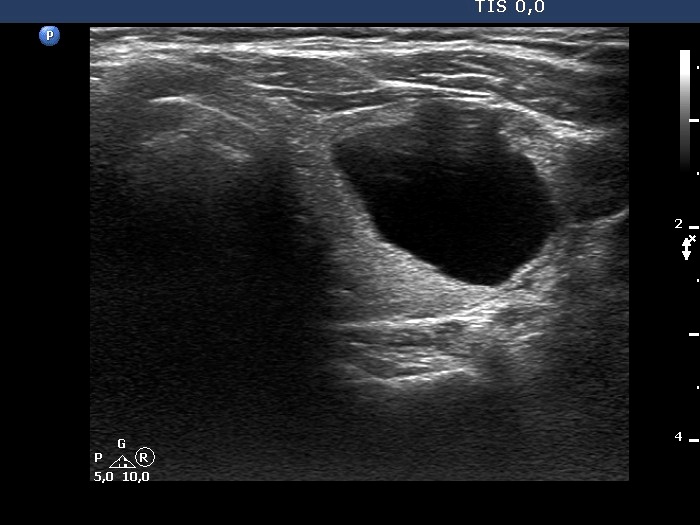

Ultrasonography. The thyroid was moderately hypoechogenic. There were two central-type cysts, one in the left lobe and another one in the right lobe. Both had perinodular vascularization.4 mL serous fluid was aspirated. Aspiration cytology resulted in benign cystic lesion.

This case illustrates how a spongiform type cyst might evolve from a central-type cystic nodule. See video and longitudinal scans of the right lobe.

The nodule has tiny hypoechoic areas, therefore the lesion can be regarded as an EU-TIRADS 4 lesion. Nevertheless, the hypoechoic areas do not raise the possibility that they would represent another pathological entity, therefore, is seems to be more accurate to classify the nodule as an EU-TIRADS 3 lesion.